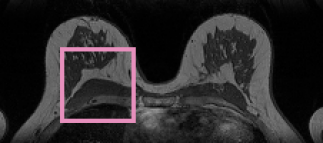

A single CNN is trained to segment six tissues in MR brain images, the pectoral muscle in MR breast images, and the coronary arteries in cardiac CTA. The CNN therefore learns to identify the imaging modality, the visualised anatomical structures, and the tissue classes.

Breast MRI –

34 T1-weighted MR breast images were acquired on a Siemens Magnetom 1.5 T scanner with a dedicated double breast array coil [16]. The images were acquired with in-plane voxel sizes between 1.21 and 1.35 mm and slice thicknesses between 1.35 and 1.69 mm. All images were resampled to isotropic voxel sizes corresponding to their in-plane voxel size. The pectoral muscle was manually segmented in the axial plane by contour drawing.

Fig. 2 shows the results of the described quantitative analysis, performed at intervals of 1000 mini-batches per task. As the networks learned, the obtained Dice coefficients increased and the stability of the results improved. For each segmentation task, the learning curves were similar for all experiments. Nevertheless, slight differences were visible between the obtained learning curves. To assess whether these differences were systematic or caused by the stochastic nature of CNN training, the training experiment using only brain MR data (Experiment 1) was repeated (dashed line in Fig. 2), showing similar inter-experiment variation. Fig. 3 shows a visual comparison of results obtained for the three different tasks. For all three tasks, all four networks were able to accurately segment the target tissues.